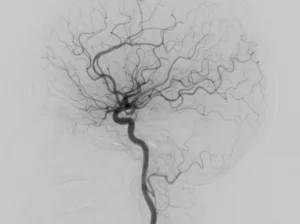

• Angiografia cerebral